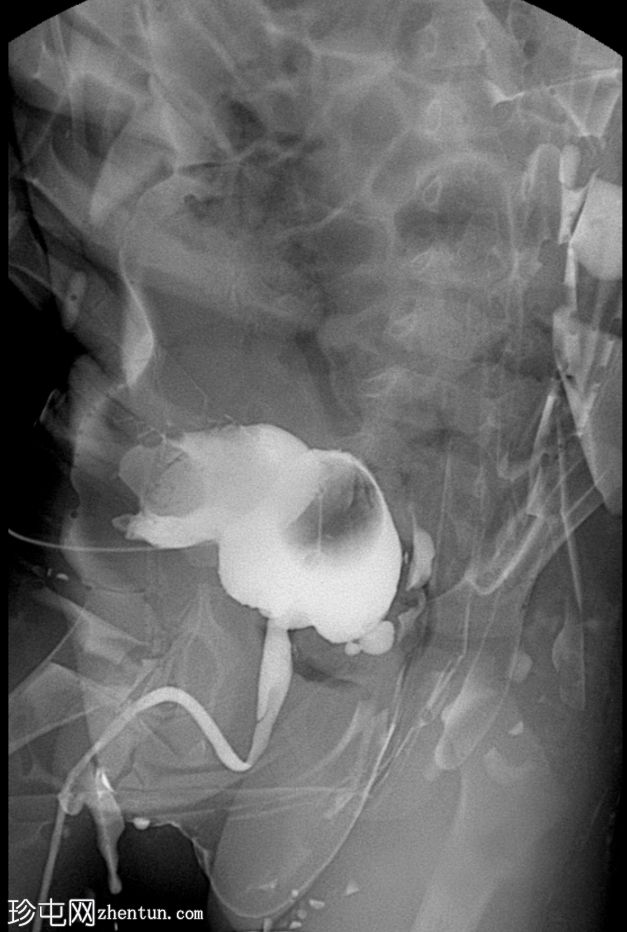

正位片(含Foley导尿管球囊)

可见脐尿管开口通畅;在充盈期,造影剂经脐尿管自由流出,导致膀胱充盈不足。经脐尿管开口置入Foley导尿管并充盈球囊;然而,造影剂持续渗漏,膀胱充盈仍然不足。